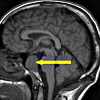

Целью генодиагностики атаксии-телеангиэктазии (синдрома Луи-Бара) является выявление прогрессирующего мультисистемного поражения с аутосомно-рецессивным типом наследования. Патология вызвана мутациями в гене ATM (11q 22-23), который кодирует протеин серин-треонинкиназу ATM, участвующий в репарации двухцепочечной ДНК и апоптозе клеток. Примерно у 90% пациентов белок ATM полностью отсутствует, что влечет за собой развитие тяжелого классического синдрома Луи-Бар. Более мягкое течение наблюдается со следовыми количествами белка.